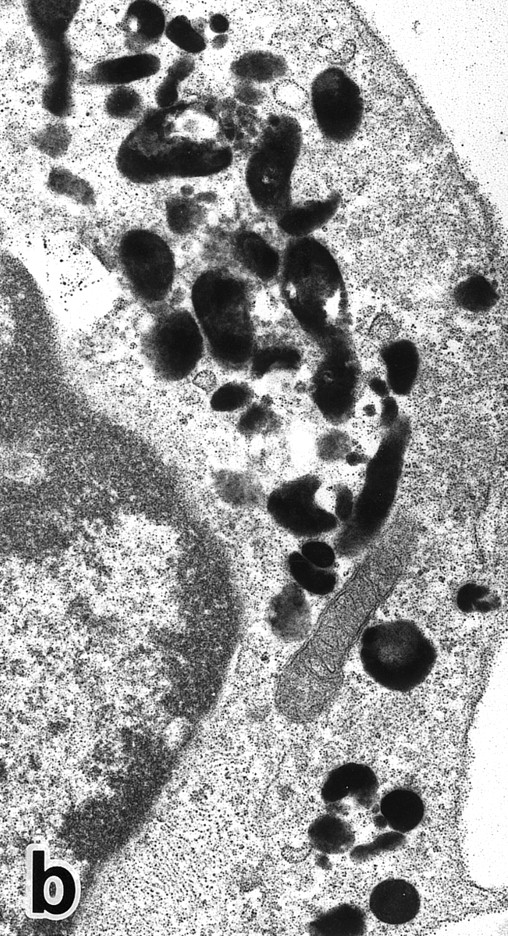

Bone marrow leukemic cells in patient no. 1 at diagnosis (a), after 1 week of ATRA treatment (b), and after 3 weeks of ATRA treatment (c). (Original magnification × 330.)

Common morphological changes of bone marrow leukemia cells were observed during ATRA treatment. After 1 week of ATRA treatment, leukemic cells showed heterochromatin condensation and nuclear lobulation (Figs 3 and 4). Although the lobulated nuclei of some cells resembled those of PMNs, these nuclei were irregular in shape and nucleoli were occasionally present. The lobulated nuclei often had nuclear blebs (Fig 3a) or were connected by thin nuclear material (Fig 4a), called filamentous connections,13 that consisted of heterochromatin delimited by the nuclear membrane. In addition to these changes, the irregularly shaped primary granules became morphologically normal. This was most evident in patient no. 1, in whom the majority of both Auer rods and irregularly shaped inclusions, as shown in Fig 2, dramatically vanished and the remaining primary granules appeared normal, being spherical in shape and relatively homogeneous in size (Fig 3a), although abnormal primary granules and/or Auer rods were infrequently observed in some cells. Rarely, a structure composed of an Auer rod coupled with a primary granule was found, appearing as though the seemingly normal primary granule had emerged from the Auer rod (Fig 3b). Type I primary granules still predominated in all patients, but type II primary granules with a nucleoid structure were rarely observed in patients no. 1 and 2. Some maturing neutrophils with abnormally shaped lobulated nuclei in patient no. 2 possessed unusual, possibly immature, primary granules containing central electron-dense material (Fig 4a and b), indicating asynchronous maturation of nuclei and cytoplasmic granules.